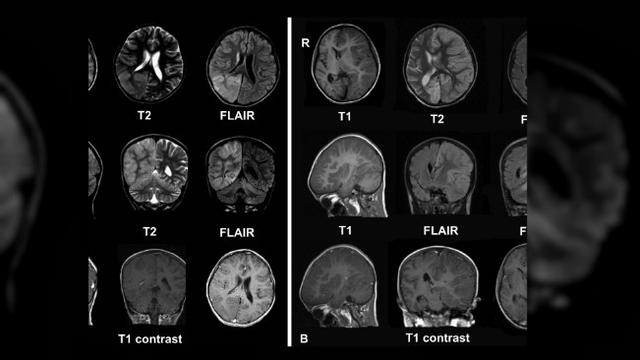

MRI dapat digunakan untuk mendeteksi dan mendiagnosis berbagai macam kondisi medis pada otak, seperti stroke, tumor otak, perdarahan otak, multiple sclerosis, dan trauma otak.